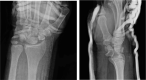

Trans-scaphoid lunate dislocation with volar displacement into the wrist/distal forearm is a devastating injury that most commonly occurs under situations of forceful impact to an extended wrist. Due to ligamentous disruption as well as fragile blood supply, these Mayfield type 4 injuries are associated with significant morbidity and long-term sequelae. Current treatment approaches to lunate dislocations depend on the severity and chronicity of the injury in addition to patient factors, with operative management potentially including ORIF or proximal row carpectomy. We report 5 cases of this rare injury pattern in 4 different patients.